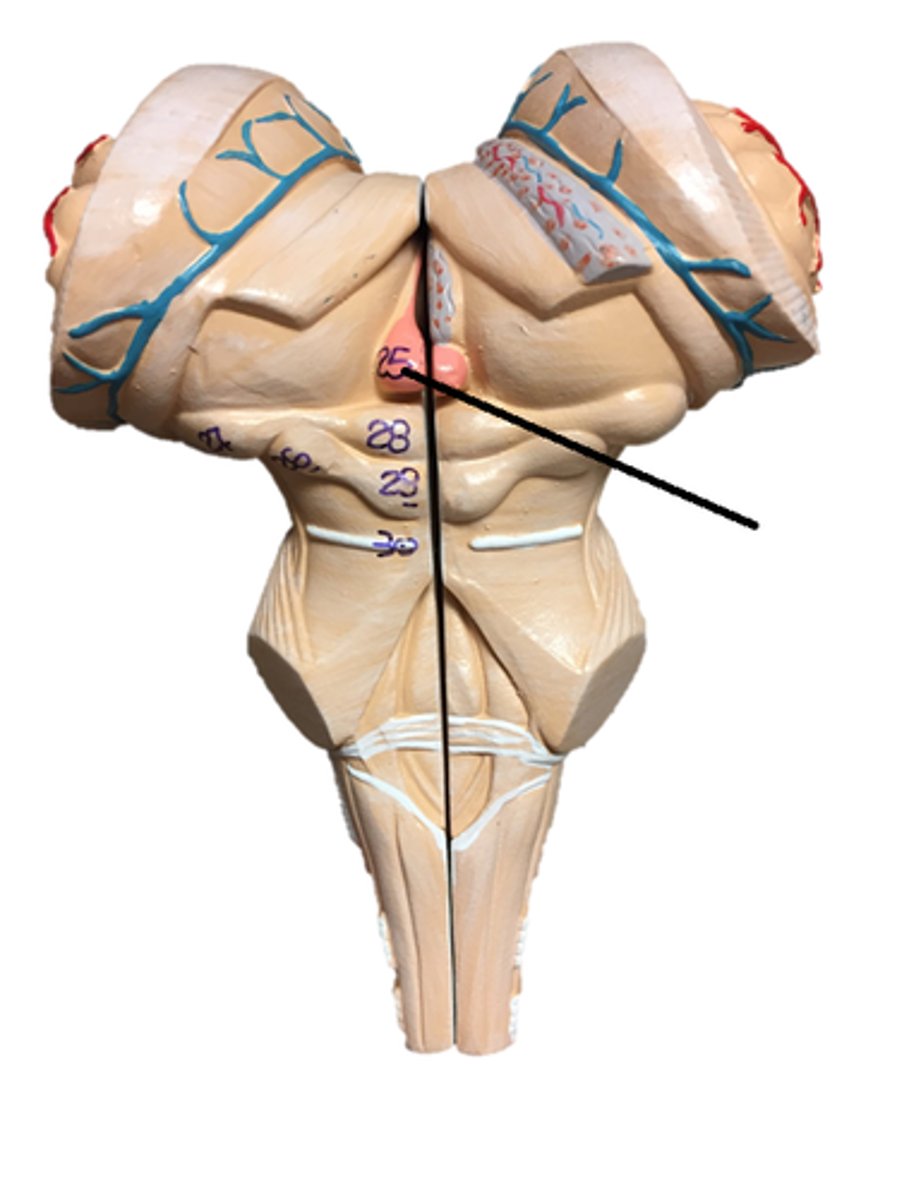

pons

midbrain

medulla oblongata

olive

superior colliculi

inferior colliculi

cerebral peduncles

vermis